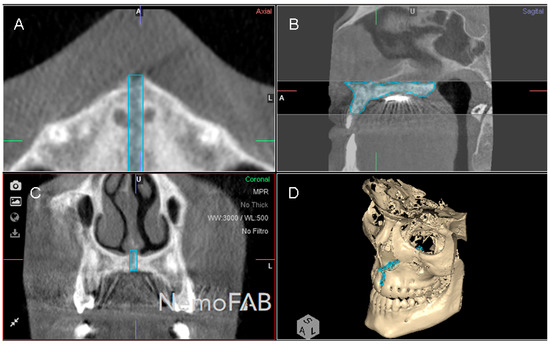

Figure 5.

(A) CBCT scan uploaded to the three-dimensional orthodontic-planning software, (B) alignment procedure of the CBCT scan, (C) alignment and (D) measurement procedure of the palatine suture expansion at the central incisors, canines and first permanent molars.

In addition, lineal measurements of the palatine suture expansion were also performed in order to analyze and compare the repeatability and reproducibility of the previously described conventional measurement technique [28,29] with the novel digital measurement method to quantify the volume of the midpalatal suture after rapid RME procedures. After uploading the images into three-dimensional orthodontic-planning software (NemoFAB 3D NemoStudio® 19.2.0 uv 89 2KT, Nemotec; Madrid, Spain) (Figure 5A), the midpalatal suture was aligned to the sagittal axis (Figure 5B) and the palatal plane was aligned to the axial axis (Figure 5C). Subsequently, horizontal lineal measurements from the cortex of the disjunction were performed at the central incisors, canines and first permanent molars (Figure 5D).